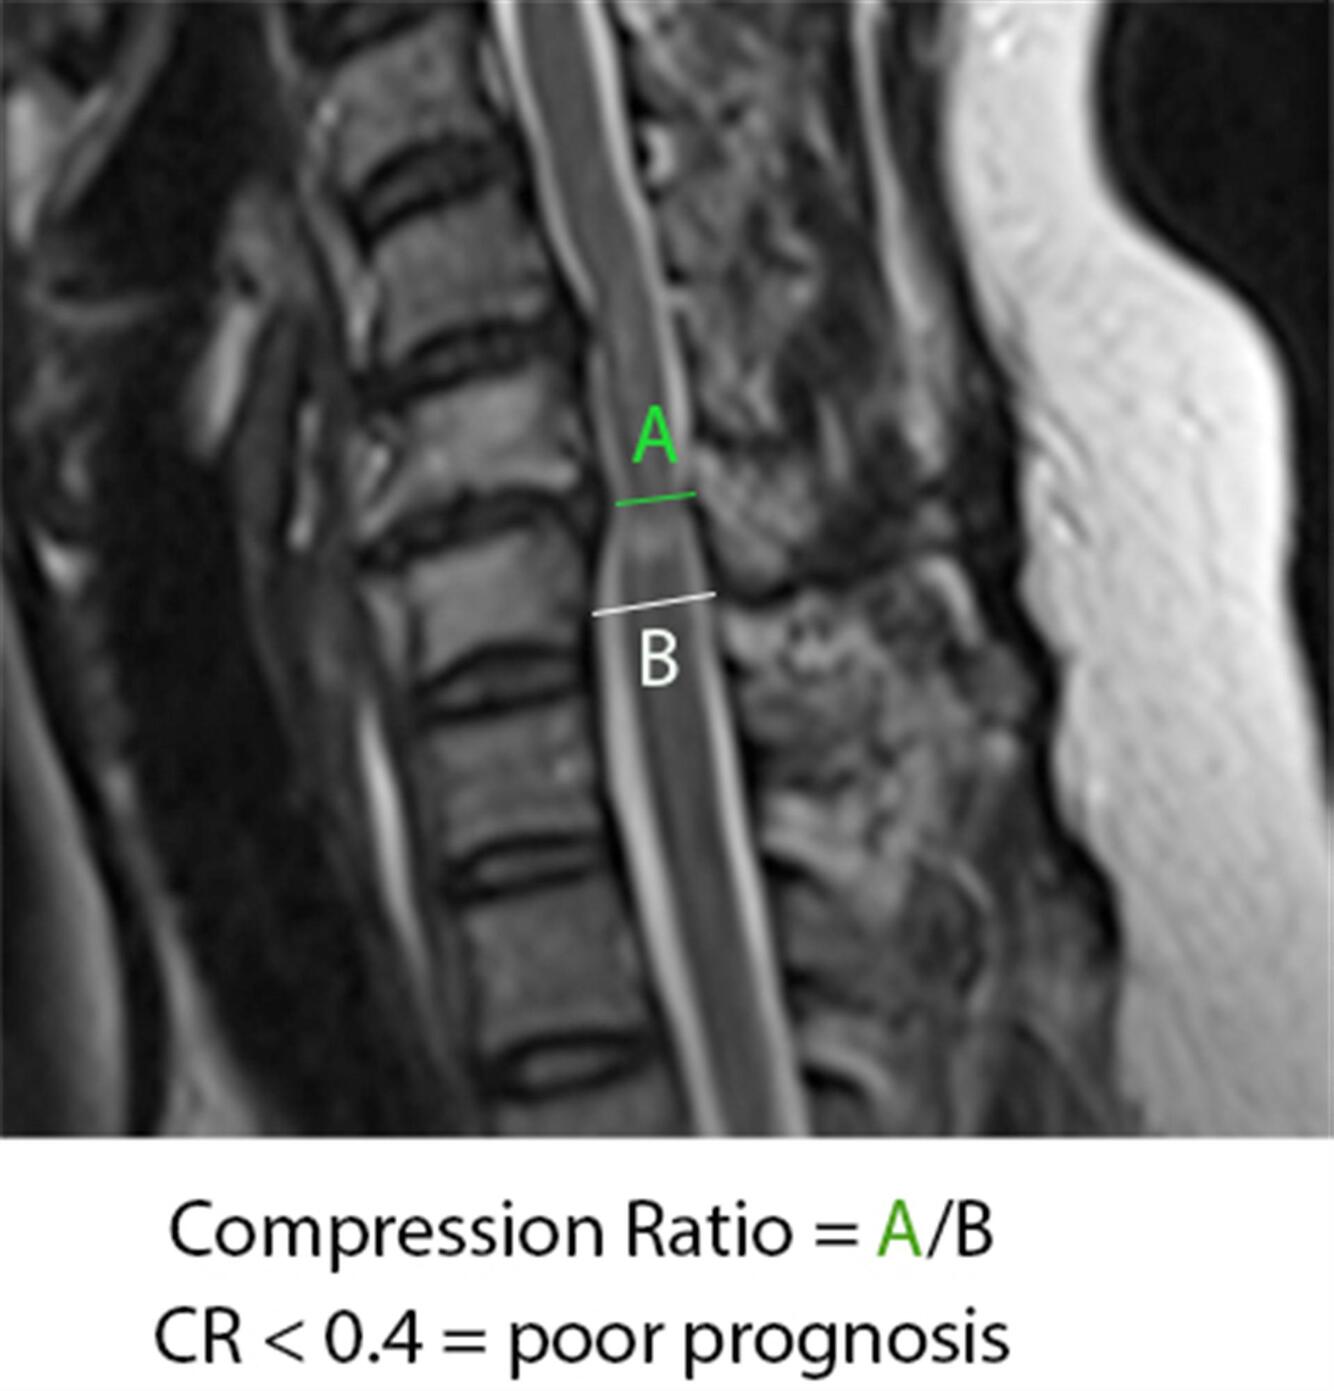

MRI: What MRI findings will you see? What correlates to poorer prognosis?

• Effacement of CSF; spinal cord changes (myelomalacia=bright signal on T2; signal changes on T1 correlate w/ poorer prognosis following decompression)

• compression ratio of < 0.4 carries poor prognosis

CR = smallest AP diameter of cord / largest transverse diameter of cord